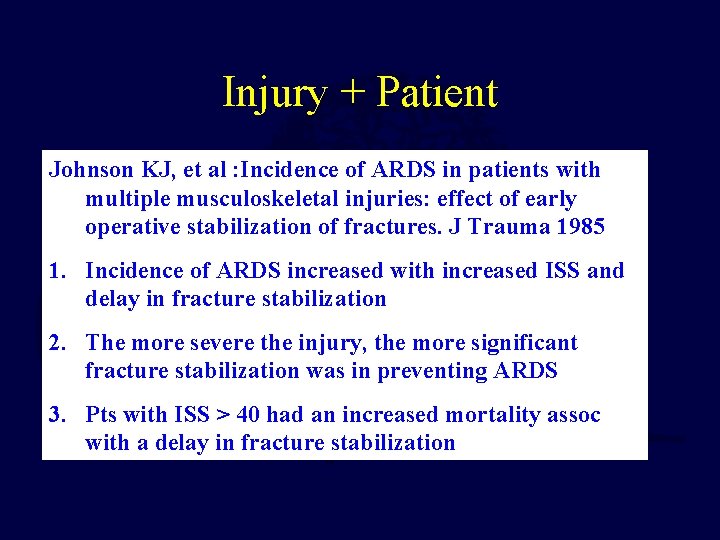

Injury + Patient Johnson KJ, et al : Incidence of ARDS in patients with POLYTRAUMA multiple musculoskeletal • Early stabilization beneficialinjuries: effect of early operative stabilization fractures. J Trauma 1985 » Seibel Ann of Surg 1985 Bone, JBJS 1989 1. Incidence of» ARDS increased with increased ISS and » Goris , J Trauma 1982 delay in fracture stabilization » Johnson, J Trauma 1985 » Behrman, J Trauma 2. The more severe the injury, the 1990 more significant » Bone, J Trauma fracture stabilization was in 1994 preventing ARDS 3. Pts with ISS > 40 had an increased mortality assoc with a delay in fracture stabilization

Injury + Patient Practice management guidelines Recommendations-Polytrauma • Level II-no improvement in survival some patients fewer complications - no detrimental effect of early fixation - early fixation preferable - Dunham J Trauma 2001